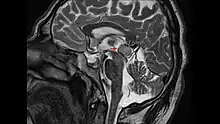

Le diagnostic repose en premier lieu sur l'IRM du cerveau, puis le type histologique[8] de la tumeur est précisé par une biopsie stéréotaxique, réalisée par un neurochirurgien. On profite généralement de cette opération pour réaliser, en plus une ventriculocisternostomie[8], pour permettre l'écoulement du liquide cérébro-spinal, ou liquide céphalo-rachidien en ancienne nomenclature. Ce geste est essentiel pour réduire l'HTIC, qui demeure une urgence médico-chirurgicale.